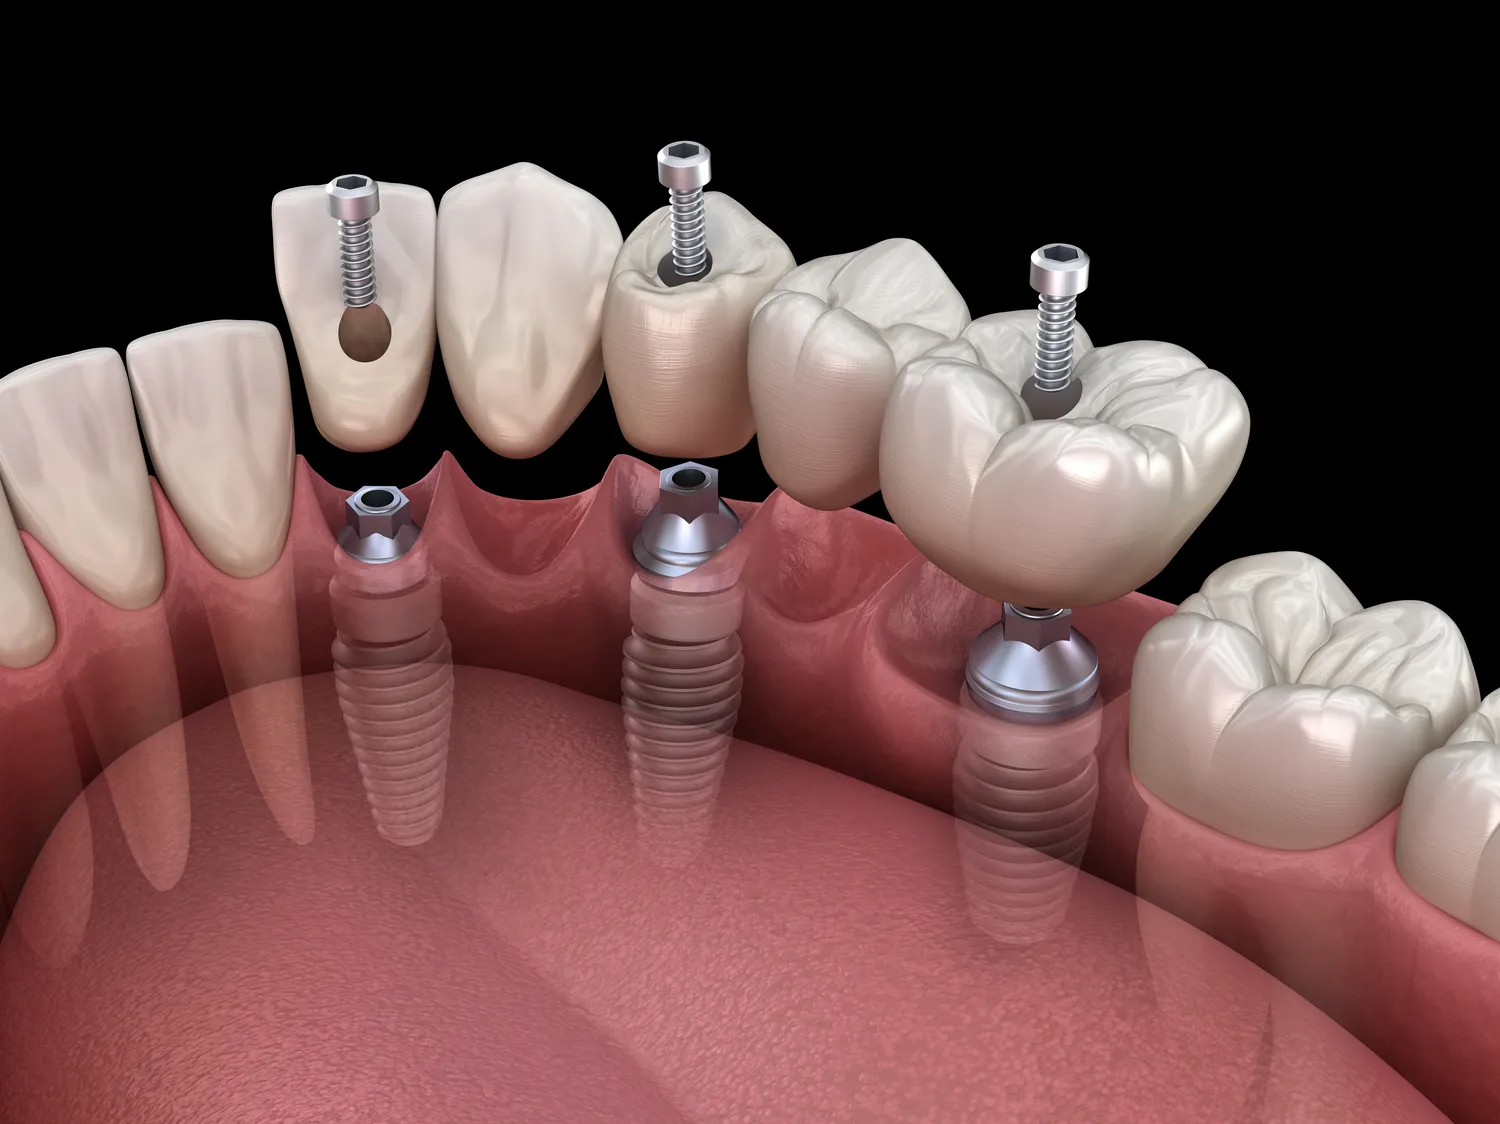

Stomatologia to dziedzina medycyny, która zajmuje się diagnostyką, leczeniem oraz profilaktyką chorób jamy ustnej i zębów. W ramach stomatologii istnieje wiele specjalności, które różnią się zakresem działań oraz metodami leczenia. Najpopularniejsze z nich to stomatologia ogólna, ortodoncja, periodontologia, chirurgia stomatologiczna oraz protetyka. Stomatologia ogólna koncentruje się na podstawowej opiece dentystycznej, w tym na leczeniu próchnicy, usuwaniu zębów oraz wykonywaniu przeglądów stomatologicznych. Ortodoncja natomiast zajmuje się korygowaniem wad zgryzu oraz ustawienia zębów za pomocą aparatów ortodontycznych. Periodontologia to specjalność skupiająca się na chorobach przyzębia i tkankach otaczających zęby, a chirurgia stomatologiczna obejmuje bardziej skomplikowane zabiegi operacyjne, takie jak usuwanie ósemek czy wszczepianie implantów.

Współczesna stomatologia korzysta z wielu nowoczesnych technologii, które znacząco poprawiają jakość leczenia oraz komfort pacjentów. Jednym z takich rozwiązań jest cyfrowe obrazowanie, które pozwala na dokładną diagnostykę stanu uzębienia oraz tkanek miękkich. Dzięki tomografii komputerowej możliwe jest uzyskanie trójwymiarowych obrazów struktur anatomicznych, co ułatwia planowanie skomplikowanych zabiegów chirurgicznych czy implantologicznych. Kolejnym innowacyjnym rozwiązaniem są lasery stomatologiczne, które umożliwiają precyzyjne usuwanie tkanek oraz przeprowadzanie zabiegów bez bólu i krwawienia. W protetyce coraz częściej stosuje się technologię CAD/CAM do projektowania i produkcji indywidualnych koron czy protez, co skraca czas oczekiwania pacjentów na wykonanie tych prac. Dodatkowo rozwój materiałów stomatologicznych sprawił, że dostępne są nowoczesne kompozyty o wysokiej estetyce i trwałości, które doskonale imitują naturalne zęby.

Najnowsze trendy w stomatologii mają ogromny wpływ na jakość leczenia oraz komfort pacjentów. Jednym z najważniejszych kierunków rozwoju jest cyfryzacja procesów diagnostycznych i terapeutycznych. Dzięki zastosowaniu technologii takich jak skanery wewnątrzustne czy druk 3D możliwe jest szybkie i precyzyjne wykonanie modeli anatomicznych oraz planowanie zabiegów. To z kolei przekłada się na krótszy czas oczekiwania na wykonanie prac protetycznych oraz większą dokładność ich dopasowania do indywidualnych potrzeb pacjentów. Kolejnym istotnym trendem jest rosnąca popularność minimalnie inwazyjnych technik leczenia, które pozwalają na zachowanie jak największej ilości zdrowej tkanki zęba podczas przeprowadzania zabiegów. Przykładem takiej metody jest ozonoterapia, która wykorzystuje właściwości ozonu do zwalczania bakterii odpowiedzialnych za próchnicę bez konieczności borowania. Również rozwój telemedycyny umożliwia pacjentom konsultacje ze specjalistami bez konieczności osobistego stawienia się w gabinecie, co jest szczególnie istotne dla osób z ograniczoną mobilnością lub mieszkających w odległych lokalizacjach.